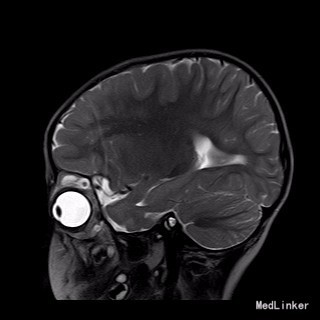

2岁9月患儿,因“左眼睑下垂1年余,头痛、呕吐8天”入院。家属1年前发现患儿左侧眼睑下垂,无法自行张开,一直未予特殊诊治。8天前患者哭闹频繁,诉头痛如爆炸样,剧烈难忍,并出现呕吐胃内容物数次,无伴抽搐、视力下降,无意识障碍。当地医院头颅MRI提示:左侧眼眶扩大,左侧眼球外上方泪腺区见一条状迂曲异常信号影,T1WI呈等信号,T2WI上病灶外缘呈高信号,内为等信号,增强扫描病灶中央呈条状明显强化影,边缘无明显强化,双侧大脑半球对称,灰白质对比正常,未见局灶性信号异常,左侧中颅窝前分蛛网膜下腔增宽,内为脑脊液信号;各脑室、脑池大小、形态均正常,中线结构居中,幕下小脑、脑干无异常,矢状面示垂体大小形态正常,未见局灶性信号异常;增强扫描未见明显异常强化。

查体见眼球稍向前突出,皮下可触及结节状软性肿物,缺乏边界,无搏动性眼球突出。左眼睑下垂,双瞳孔等圆等大,直径约2.5mm,光反射灵敏,眼球活动好,视力粗测正常,视野测试不能配合。

完善相关检查,在气管插管麻下行“左额眶部占位病变切除术”。术后病理诊断为“(左眼眶)丛状神经纤维瘤”。术后给予患儿脱水、营养脑神经、抗感染等对症治疗。复查CT未见明显异常。

患儿术后2周左眼睑下垂较术前好转。双侧瞳孔反射、眼球活动均无异常。 丛状神经纤维瘤主要发生于眼睑,在出生后或幼年时期即出现症状和体征。侵袭范围广泛,包括眼睑、眶内软组织、眶骨和邻近的脑、颞部等。眼部最早和最多见为上、下睑软性肥厚,皮下瘤组织增生,使上、下睑隆起。眼睑皮肤常有淡棕色色素斑,眼球向前突出和向下移位。眼球突出虽然很显著,但向眶内纳入并不困难。肿瘤组织可直接侵袭眶内各种结构,上睑提肌首先被波及,引起上睑下垂,上举不足或不能。MRI可准确显示病变的范围尤其显示病变与邻近结构的关系,也可清楚显示其他部位伴发的肿瘤,但难以清晰显示眶壁骨质改变。手术治疗是必要的,手术切除应注意以下问题:1.眼睑病变的切除;2.眶内病变的处理;3.提上睑肌的处理;4.眶骨缺失的处理。丛状型术前诊断容易,但治疗较为棘手,易复发。